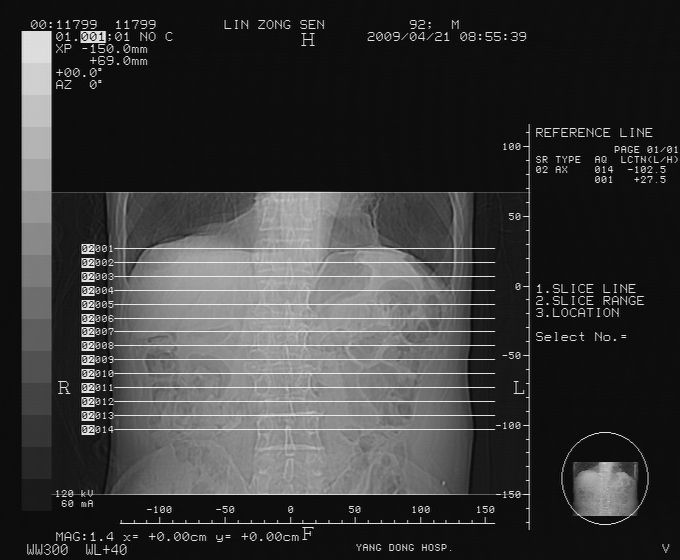

以下是引用卜一在2009-4-22 4:08:00的发言:[br]右肾积水伴输尿管上段积水!左侧肾多发囊肿!左侧腹壁软组织增厚,层次模糊,内密度较高—不排除血管瘤伴出血!